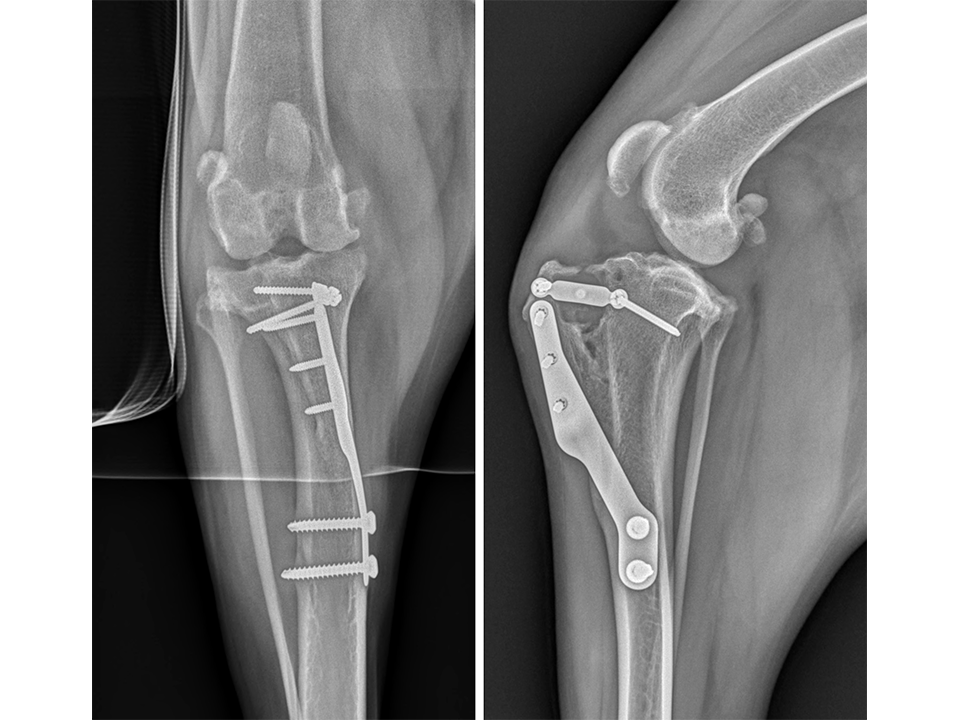

Immediate postoperative radiographs (Fig 7) revealed satisfactory implant and osteotomy positioning. Radiographs obtained 10 weeks postoperatively (Fig 8) showed no evidence of implant-associated complications and partial bone healing within the osteotomy gap. Osteoarthritic changes within the joint were static. Clinically at this stage, mild bilateral pelvic limb lameness was apparent bilateral stifle joint effusion. The left stifle joint was stable in CrTT with no pain response upon stifle joint manipulation.

The patient presented again 11 months postoperatively for assessment of right pelvic limb lameness associated with CrCL rupture. At this stage severe right pelvic limb lameness was evident but no lameness of the left pelvic limb was observed. While the right stifle joint was unstable in cranial drawer and CrTT, the left stifle remained stable with no pain response upon palpation over the implants and a normal range of motion of the joint. Radiographs of the previously operated left stifle (Fig 9) revealed no implant-associated complications and healing of the osteotomy. The osteoarthritic changes were static radiographically. TTA was performed on the right tibia at this time using a 13.5 mm wedge and a size 6 plate as had been used on the left previously.